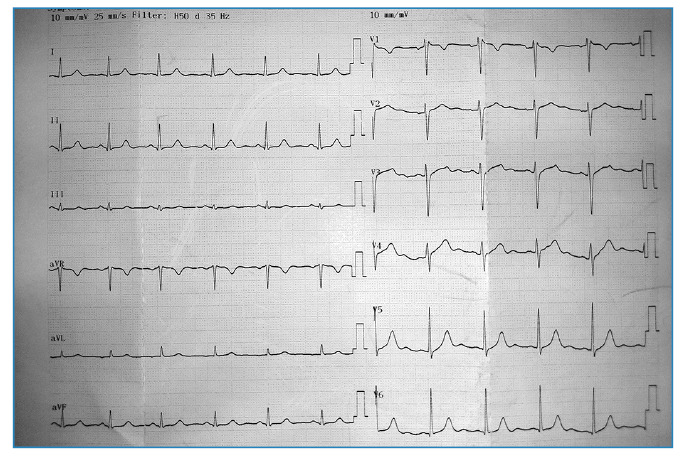

克里米亚-刚果出血热(CCHF)是一种由奈罗病毒引起的蜱传病毒性出血热,以发热、肌痛、关节痛和出血表现为特征。严重的心动过缓是这种疾病的罕见并发症。我们报告了一位30岁的男性慢性心力衰竭患者,他出现了严重的心动过缓,通过静脉注射和口服茶碱成功治疗。本病例强调了在CCHF中认识心脏并发症的必要性,并强调了药物干预在改善患者预后方面的作用。

Crimean-Congo hemorrhagic fever (CCHF) is a tick-borne viral hemorrhagic fever caused by Nairovirus and characterized by fever, myalgia, arthralgia, and hemorrhagic manifestations. Severe bradycardia is a rare complication of the disease. We present a 30-year-old male patient with CCHF who developed severe bradycardia, which was successfully treated with intravenous and oral theophylline. This case highlights the need to recognize cardiac complications in CCHF and highlights the role of pharmacological interventions in improving patient outcomes.